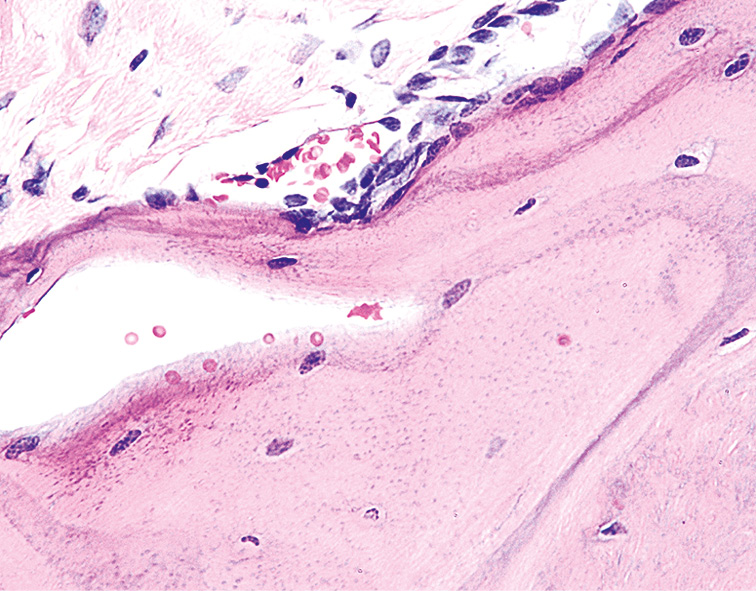

Гистологическое исследование позволило установить, что через 1 мес от начала эксперимента в слизистой оболочке пасти (СОП) животных выявляли морфологические изменения ткани с неравномерной атрофией, сглаживанием эпителиальных сосочков и гиперхромией клеток базального слоя. Под эпителием в клеточно-волокнистой строме определялись единичные кровеносные сосуды, а также пласты хрящевой ткани, в основном веществе которой видны единичные зрелые хондроциты (рис. 1).

Рис. 1. Слизистая оболочка пасти животного (опытная группа) через 1 мес от начала эксперимента. Окраска гематоксилином и эозином, ×120.

Fig. 1. The mucous membrane of the animal’s mouth (experimental group) after 1 month from the start of the experiment. Staining with hematoxylin and eosin, ×120.